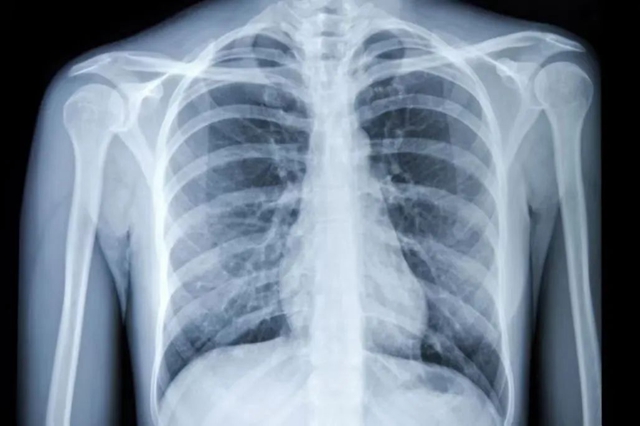

健康的肺

正常健康的肺,在X光和CT上都是透光的,并且显示为“黑色”。但如果肺部有严重的疾病(如肺炎或者肺部肿瘤),或者有大量的胸腔积液,让健康的肺组织不再具有正常的通气和其他交换功能,肺泡组织被破坏了,这时候在X光和CT上就表现为“白色”。